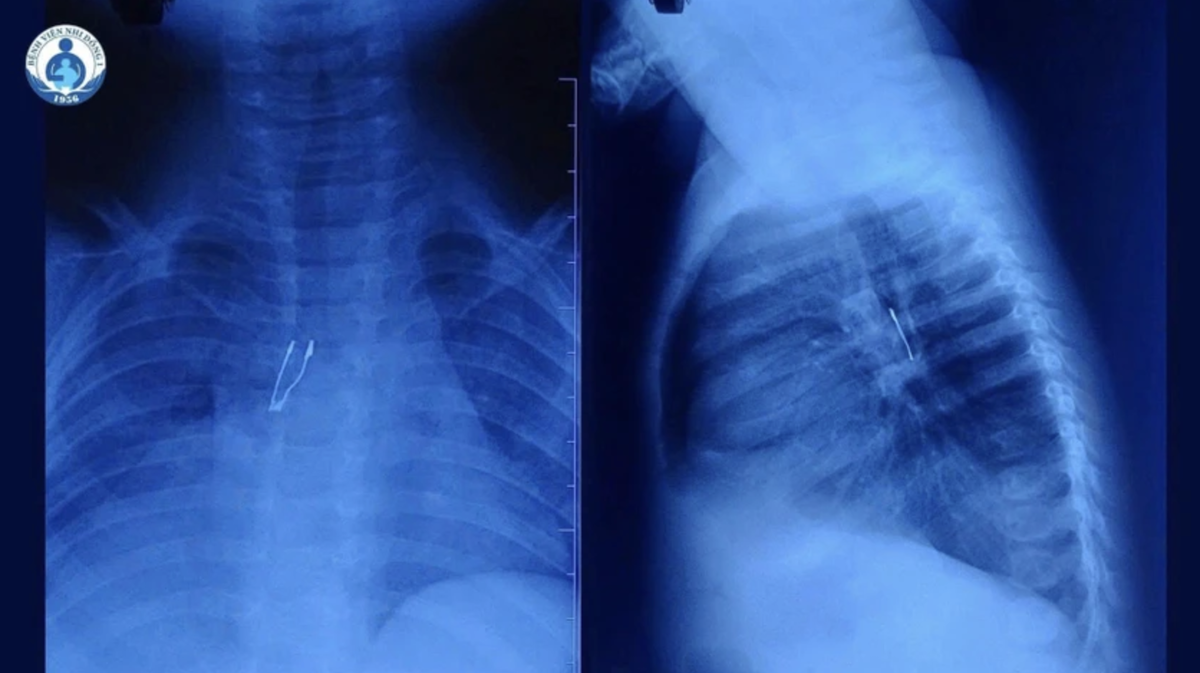

Dị vật nghi ngờ là một bóng đèn LED, nằm sâu trong phế quản gốc phải. Ảnh: BVCC

Kết quả chụp X-quang tại bệnh viện cho thấy dị vật cản quang nằm ở phế quản gốc phải, kèm theo tình trạng xẹp phổi phải không hoàn toàn và tràn khí trung thất.